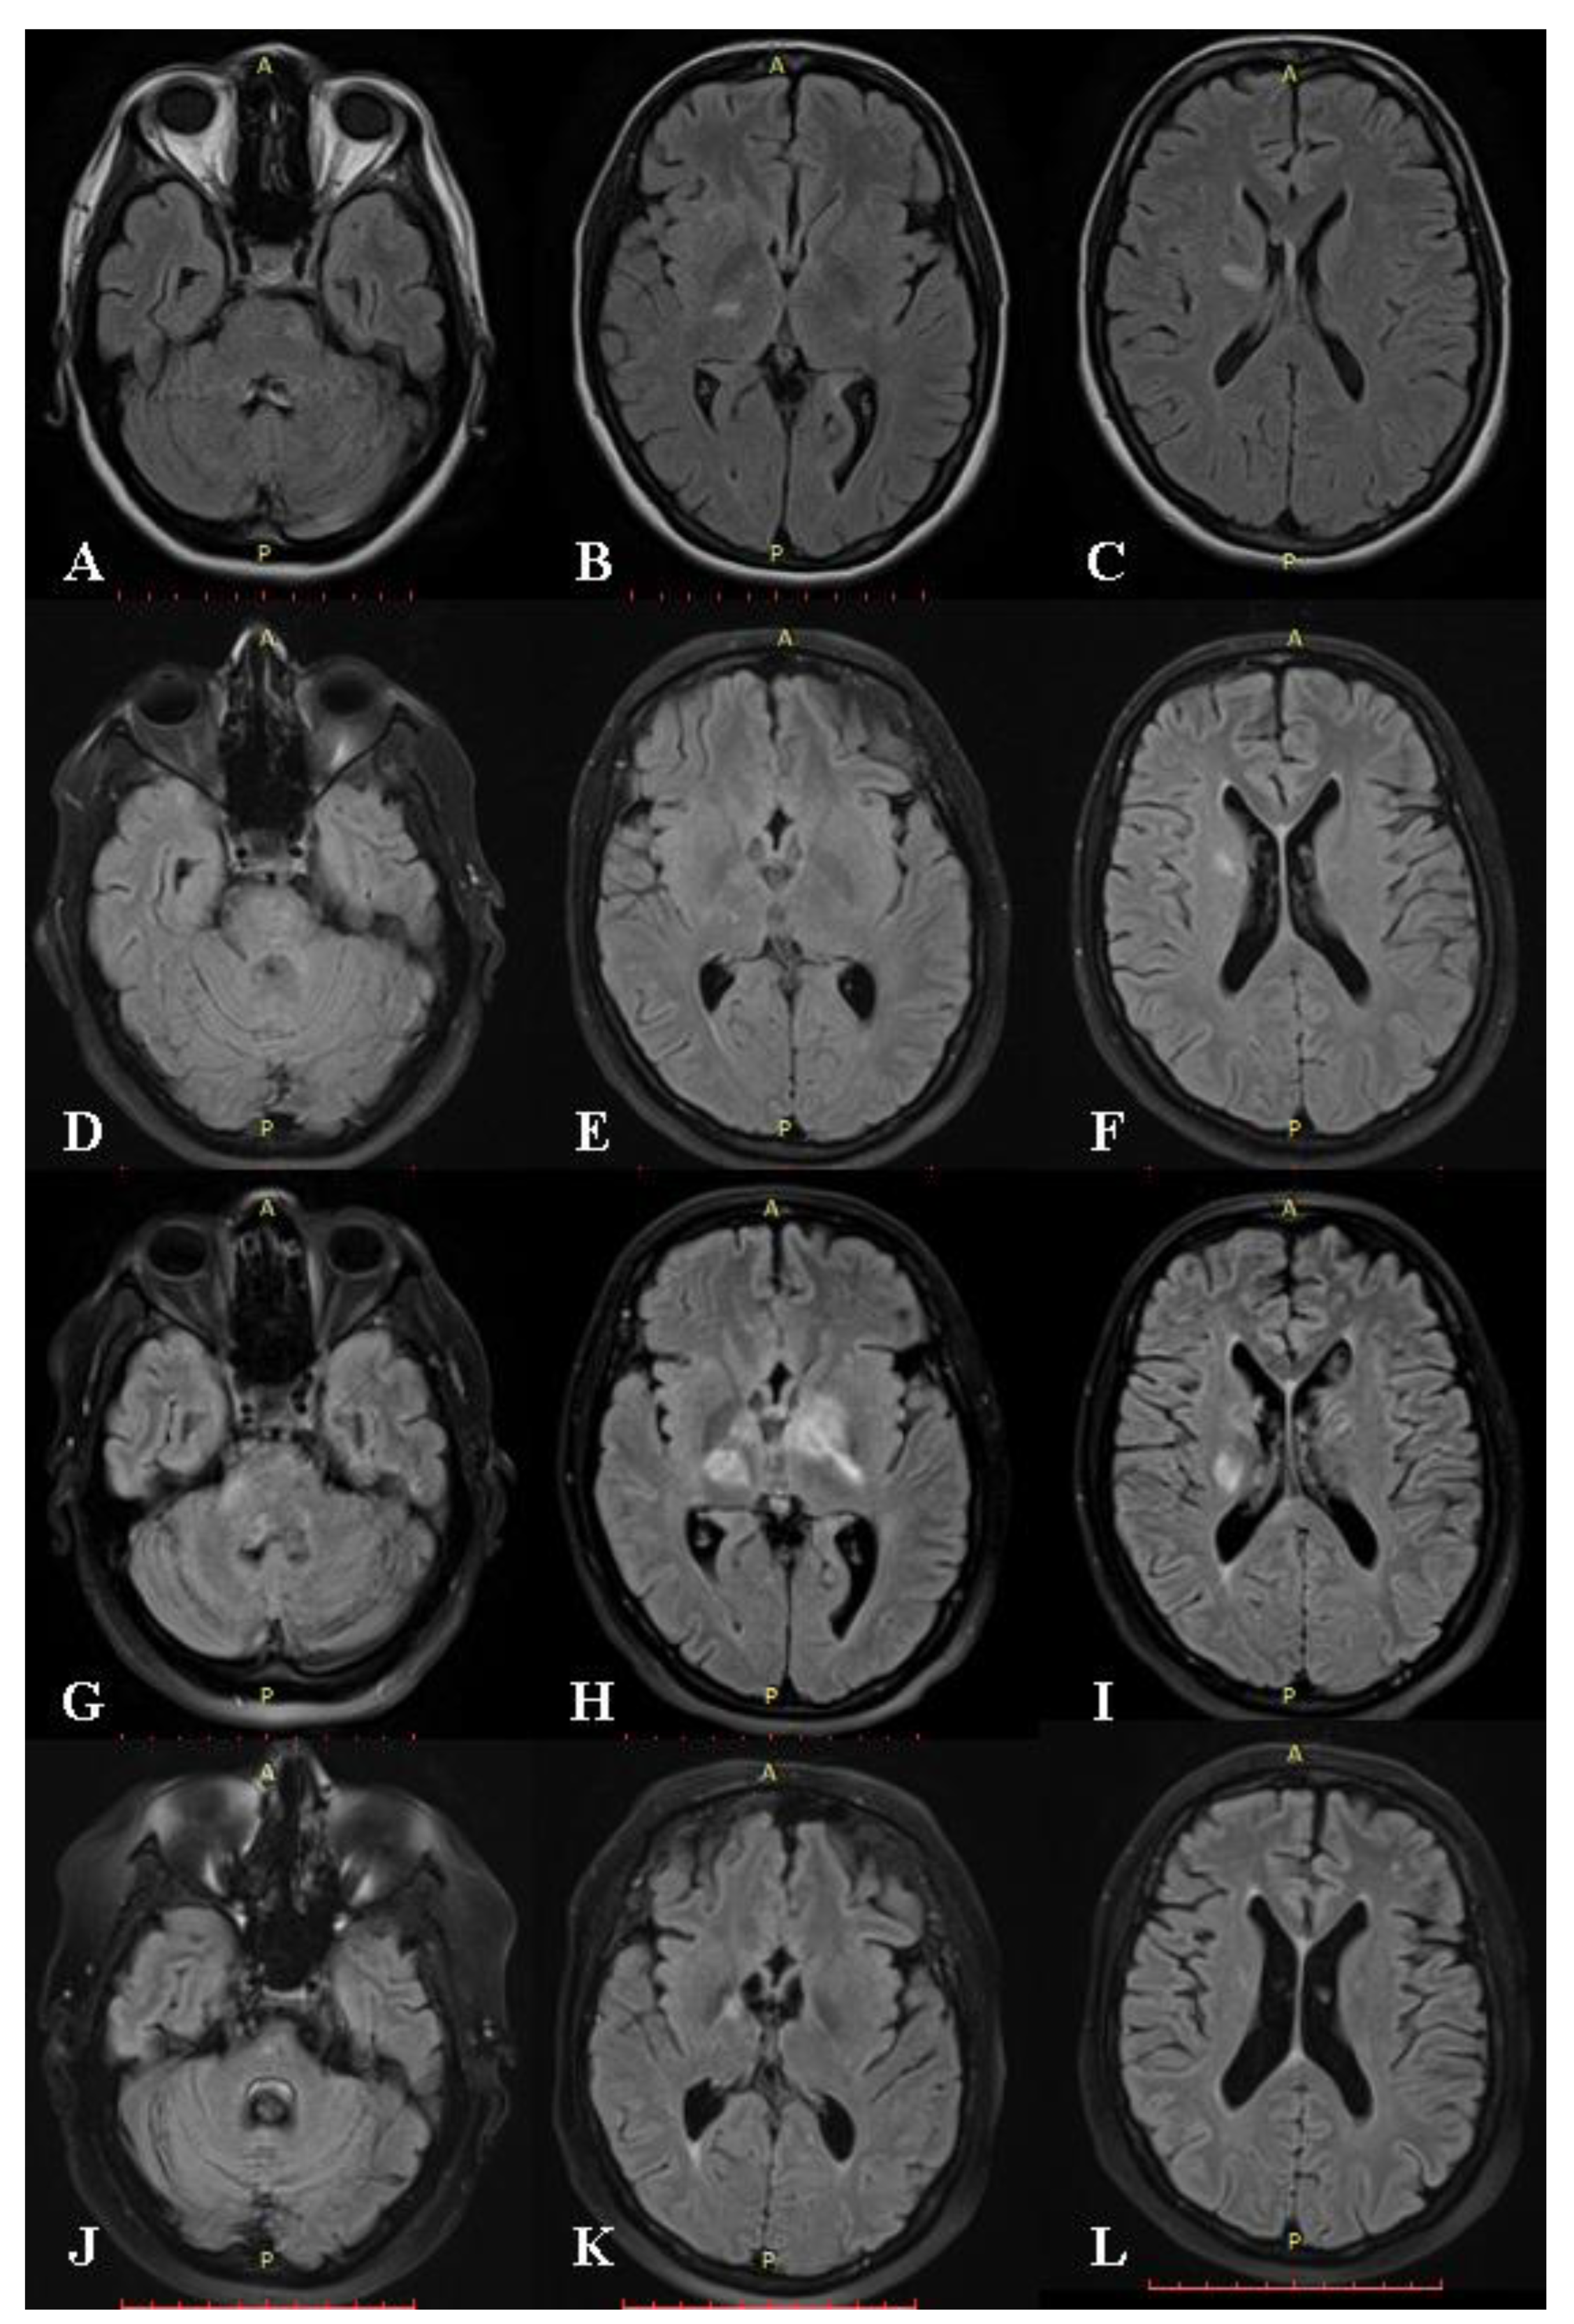

2. Case Presentation